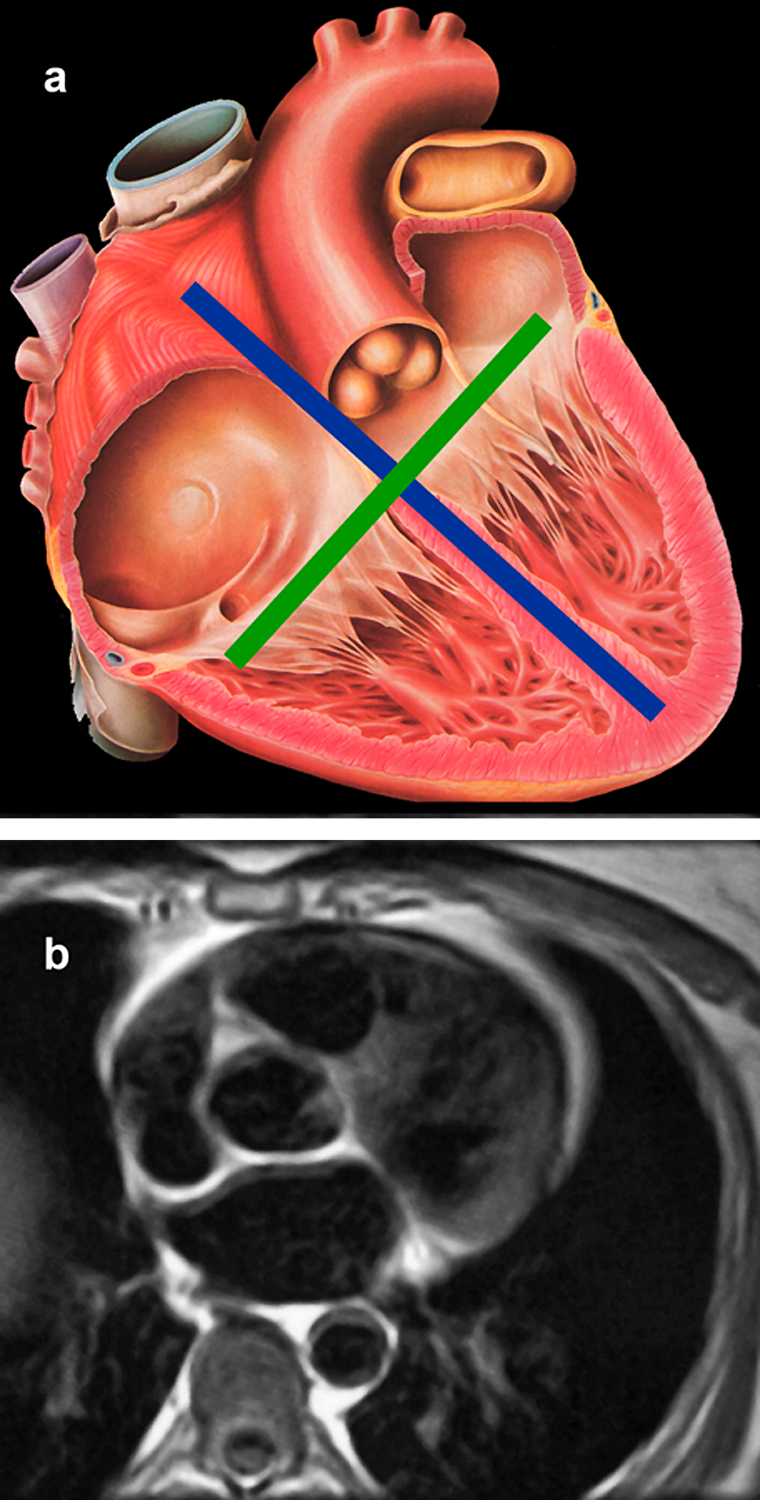

Figura 14-23:

(a) Anatomic sketch of the human heart with depic­tion of the long axis (blue) and the short axis (green).

(b)) Heart morphology: Transverse cut through the heart at the level of the aortic valve (black blood im­ages).